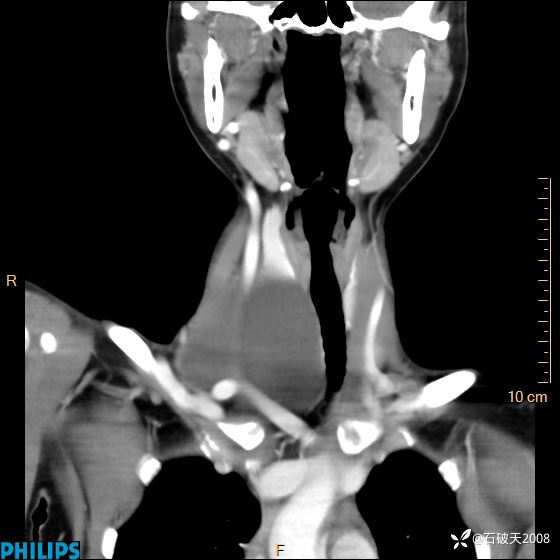

平扫

冠状位